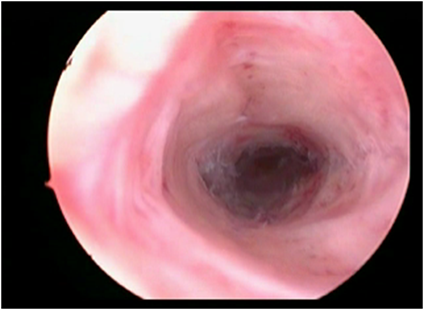

2.Septate Uterus

ह्यामध्ये गर्भाशयात पडदा निर्माण झालेमुळे गर्भाशय दुभंगले जाते.हा पडदा दुर्बिणीद्वारे ऑपरेशन करुन काढला जातो.ह्याला Septurm Excision म्हटले जाते.आपल्या हॉस्पिटलमध्ये अशाप्रकारे पडदा काढल्यानंतर बऱ्याच जणांना त्याचा लाभ झाला आहे.

septate uterus

ऑपरेशनपूर्वी

septate uterusafteroperation

ऑपरेशनंतर